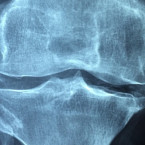

artritida

Onemocnění kloubů: Víte jakým potravinám se vyhnout, abyste zmírnili bolest kloubů?

Bolavé klouby na podzim mohou být minulostí: Stačí dodržet pár jednoduchých pravidel

Artritida: Tahle potravina vám pomůže nemoci předejít

Artritida: Netradiční aromatická ingredience, která ulevuje od bolesti

Artritida: Jak zajistit, aby se bolest kloubů nezhoršila

Světový den artritidy za dostupnou léčbu